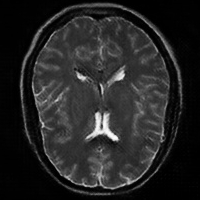

4.4 Qualitative Evaluation

In Figure 5 we analyze the prediction quality of our and compared approaches in a qualitative way. Considering modality propagation in MRI, we see that usage of uncertainty-aware patch invariance (UAPI) gives a better detailed weighting of the cerebrospinal fluid in the middle of the brain. In general, employing patch invariance yields better preservation of fine structures. This observation also applies to accelerated MRI enhancement. In particular, CUT and UAPI provide comparatively sharper knee images with more high-frequency details than the other methods.